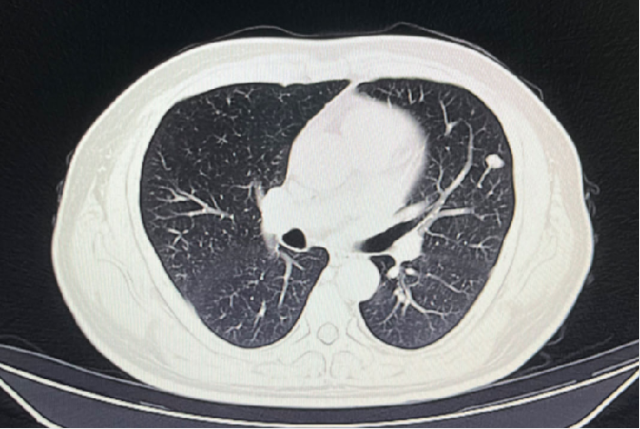

2023-05-03:

2023-08-01:

2023-11-08:

2024-02-28:

2024-05-17:

双肺多发结节

可疑结节直径较小